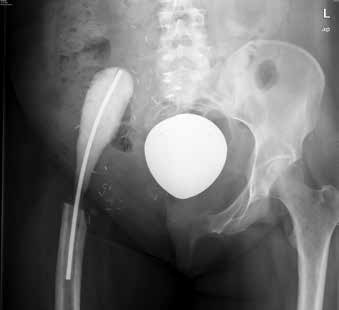

Häufige Ursachen für diese Amputationstechnik sind Osteosarkome, Chondrosarkome oder – wie im vorliegenden Fall – ein Ewing-Sarkom, das eine Resektion Typ III mit Entfernung des Os pubis umfasste 2. Dabei werden Os ilium, Acetabulum, die Beckenschaufel und der Ramus ischiadicum reseziert 3. Darüber hinaus wurde im vorliegenden Fall noch das Caput femoris entfernt. Die Bänder- und Muskelstrukturen wurden funktional angebunden.

Bei der heute 35-jährigen Klientin wurde im Oktober 2010 ein Ewing-Sarkom diagnostiziert. Eine zehnmonatige Chemotherapie begleitete die interne Hemipelvektomie mit Hüftverschiebeplastik und Spacereinbau im März 2011, daran schlossen sich zwei Monate Strahlentherapie an. Die Amputation entspricht dem Typ III A mit Entnahme des Os pubis und großräumiger Resektion der anliegenden Weichteilstrukturen 14; zudem wurde das Caput femoris entnommen; eine endbelastungsfähige Weichteilplastik kann so als Option zur Mobilisierung als wenig verlässlich angenommen werden. Die muskulären und Bänderinsertionen wurden funktional adressiert, um eine Bewegung in Richtung Hüftflexion und ‑extension zu ermöglichen (Abb. 1).

Der Spacer wurde im Oktober 2012 entnommen und eine Mutars-Prothese mit Duo-Kopf eingesetzt. Unter anderem aufgrund von Wundheilungsstörungen folgten verschiedene Revisionseingriffe. Die Mutars-Prothese wurde im November 2012 erneut durch einen Spacer ersetzt, dieser im Mai 2013 wieder explantiert und eine modifizierte Girdlestone-Situation geschaffen. Die Klientin blieb so rund 6 Jahre lang auf die Nutzung eines Rollstuhls beschränkt. Verschiedene von ihr gestartete Initiativen zu einer möglichen orthetischen Versorgung bei erfahrenen Zentren wurden dort zurückhaltend beantwortet. Auf Nachfrage standen dabei Befürchtungen hinsichtlich einer zu erwartenden möglicherweise nicht ausreichenden Mobilisierbarkeit, bezüglich der Compliance und im Hinblick auf Probleme mit dem Handling im Vordergrund. Diese nährten sich zum einen aus exemplarischen ungünstigen Erfahrungen aus vergleichbaren Versorgungsansätzen und zum anderen aus relativ suffizienten prothetischen Rehabilitationen nach externen Hemipelvektomien.